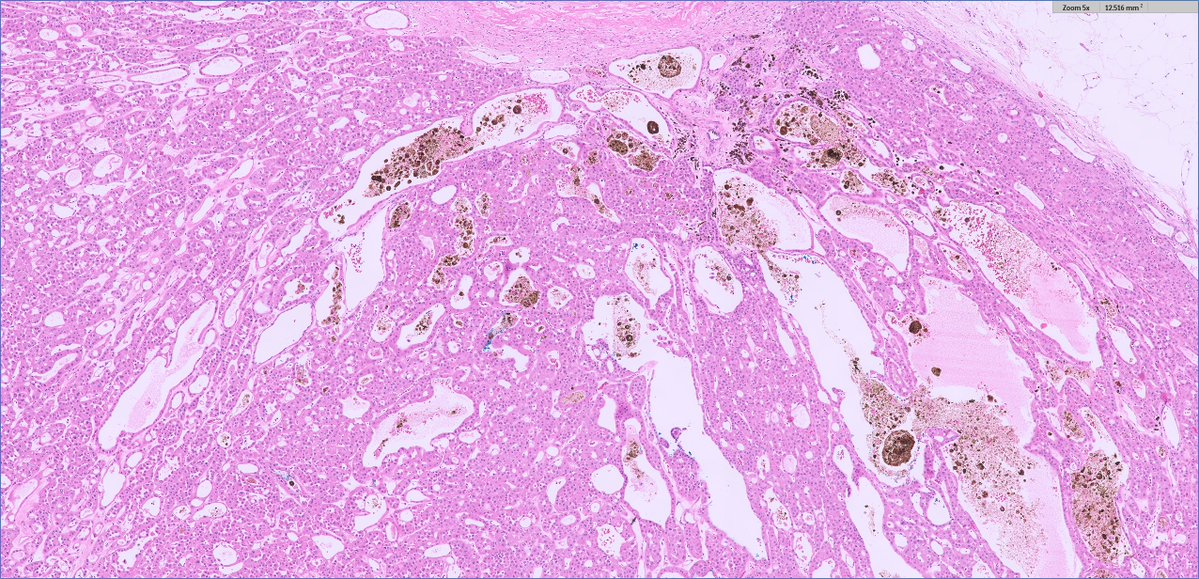

67 male with soft tissue masses, including paratesticular (1 & 2) and spleen (3) It looks like Liposarcoma but actually he had Primary Myelofibrosis for a while IHC is CD61 This is a Sclerosing extramedullay hematopoietic tumor, rare complication of Myeloproliferative neoplasms